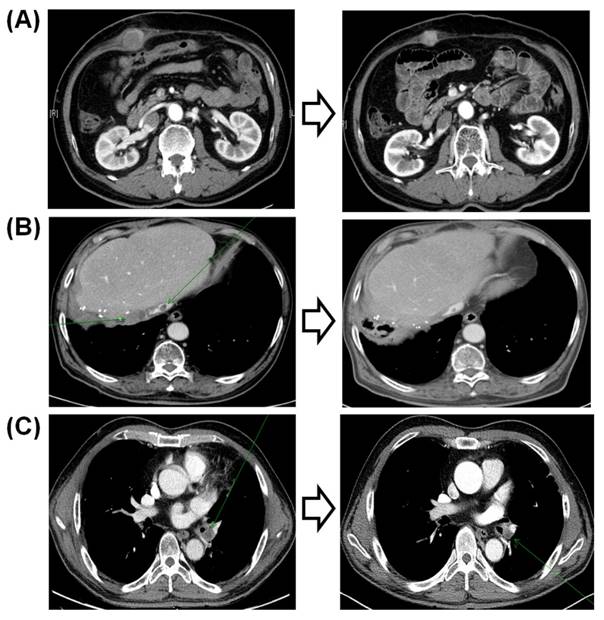

Of the three responders to sorafenib, two did not have any CNVs detected by the 21-gene NanoString panel. The first of these three patients was a 61-year-old man who was an HBsAg carrier with multiple lung metastases. The patient had an exceptional response to sorafenib, with a persistent reduction in the volumes of multiple lung metastases over 5 years (Fig. 3a). The second responder was an 84-year-old non-B non-C HCC patient with multiple metastases who responded to sorafenib for 30 months (Fig. 3b). This patient did not have any significant amplification in the 21-gene panel. The third patient, a 47-year-old man who was an HBsAg carrier with multiple lung metastases, responded to sorafenib but progressed after 9 months. This patient had KRAS and MDM2 amplifications in his tumor specimen.

Figure 3

Computed tomography findings of the three responders to sorafenib.